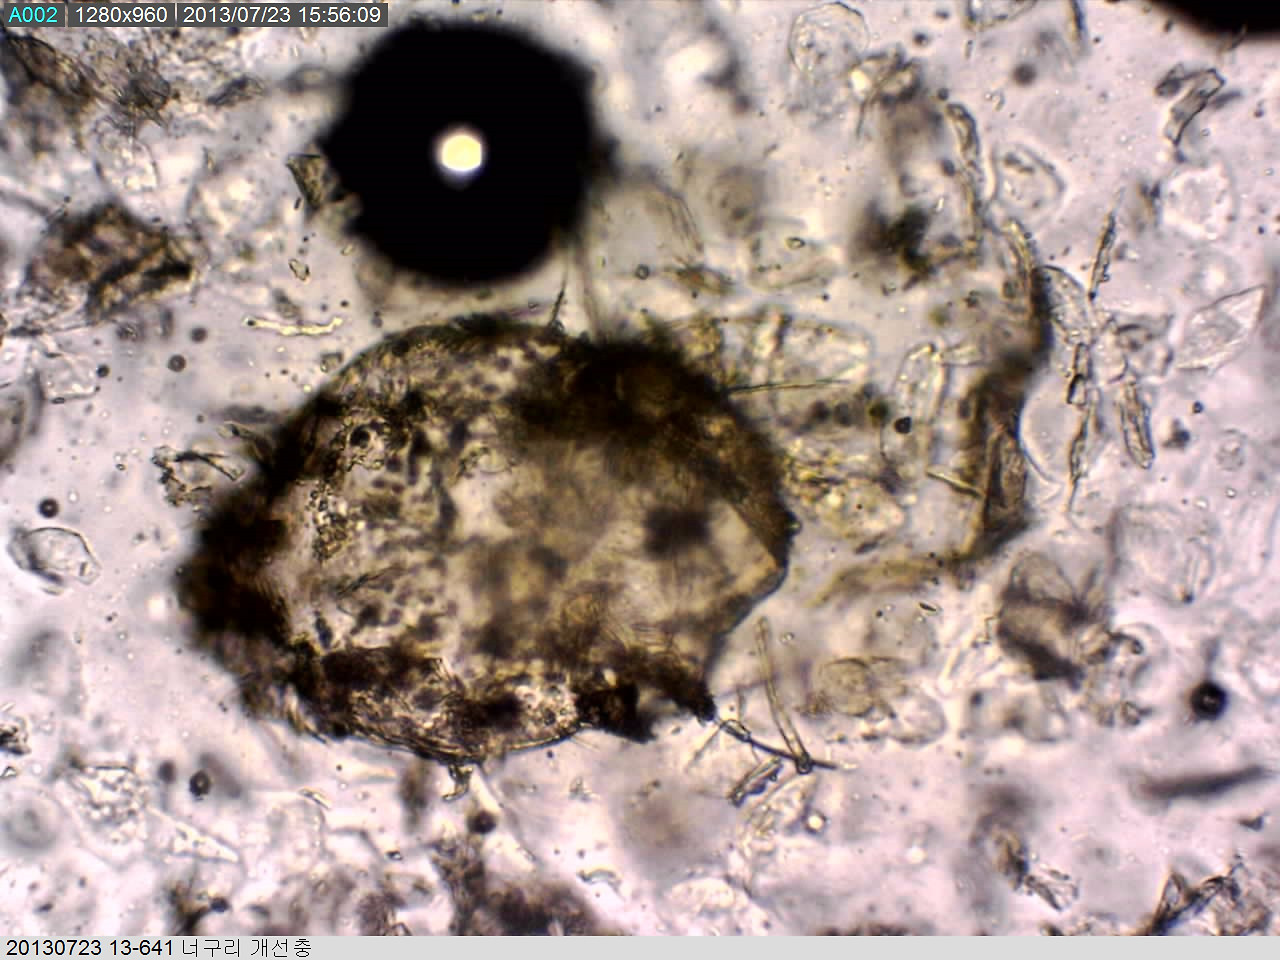

너구리 개선충 사진.jpg 이 작은 녀석이 너구리를 위협하는 '개선충'이다. 드물게 사람에게도 감염되어 가려움증을 유발하지만 생활사를 이어갈 수 없어 큰 문제를 일으키지는 않는다. 이 작은 녀석이 너구리를 위협하는 '개선충'이다. 드물게 사람에게도 감염되어 가려움증을 유발하지만 생활사를 이어갈 수 없어 큰 문제를 일으키지는 않는다.